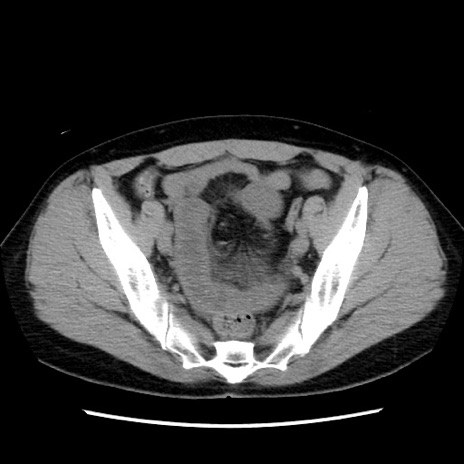

矢状断像

【症例】 50歳代女性

【主訴】 腹痛

【現病歴】前日生レバーを食べた。今朝に排便あり。 昼前に突然発症の腹痛を生じ、当院救急外来を受診した。

【既往歴】 子宮筋腫にてで子宮全摘後

【身体所見】 意識清明、腹部:平坦、軟、下腹部やや左を中心に圧痛・反跳痛あり、筋性防御あり

【データ】WBC 7800、CRP 0.07